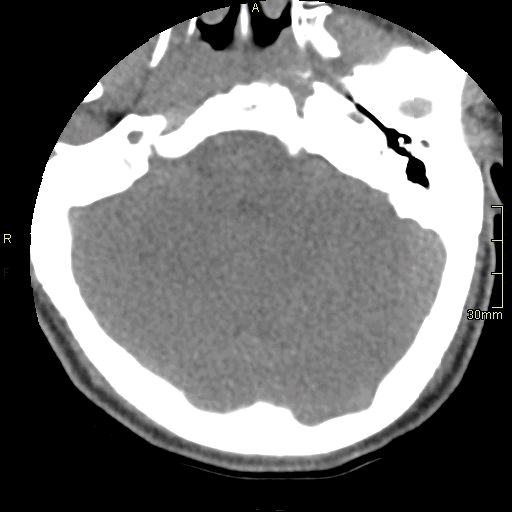

CT Cervical Spine Non Contrast- Soft Tissue window (axial)

CT Cervical Spine Non Contrast- Soft Tissue window (coronal)

CT Cervical Spine Non Contrast- Soft Tissue window (sagittal)